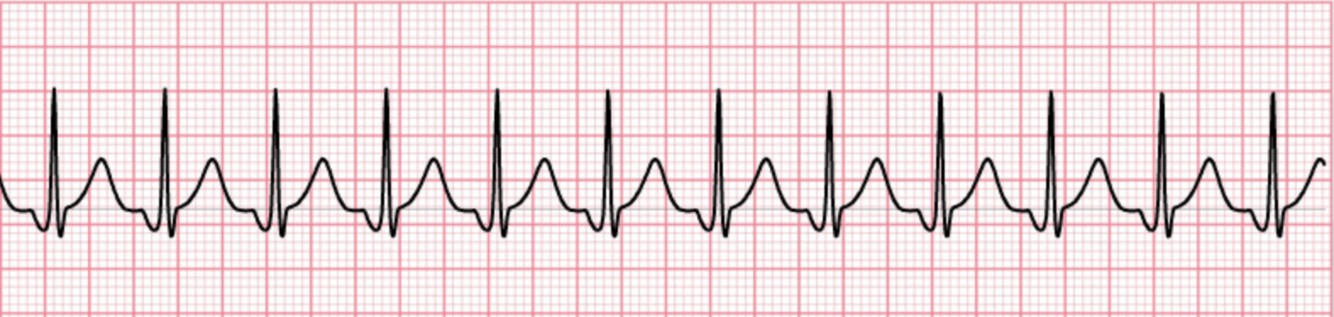

8

Q

Which rhythm is this?

A

Accelerated Junctional Rhythm

• Normal QRS complexes without a preceding P wave, inverted P wave, late P Wave

• Heart Rate: 61-100 bpm